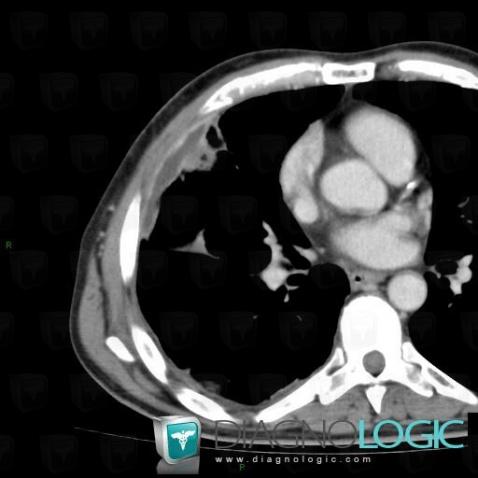

Empyema, Pleura, CT

Here is the specific information in the key image above:

- Diagnosis Empyema, Location(s) Pleura, with gamuts Pleural thickening, Solitary pleural mass